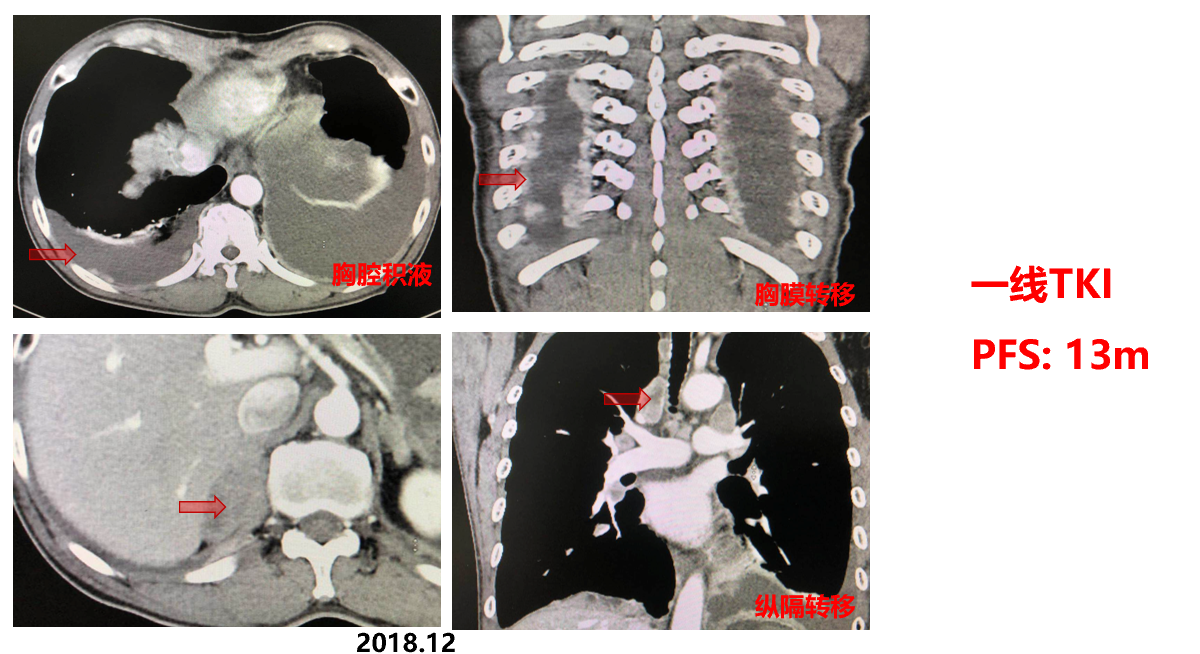

一线培唑帕尼(赛贝欣, 800mg QD ): 部分缓解(PR)

一线TKI 13个月:肿瘤进展

二线TKI(索拉菲尼400mg BID) 治疗3月:肿瘤继续进展

三线治疗:减量培唑帕尼+PD-1单抗,治疗2月达PR;维持用药,疗效持续稳定

2020.04:间断使用免疫药物,单用培唑帕尼维持;

2020.09:复查CT:整体稳定控制;

2023.12:PD-1单抗维持治疗,复查CT:整体稳定控制;

从一线TKI 开始OS:90+月